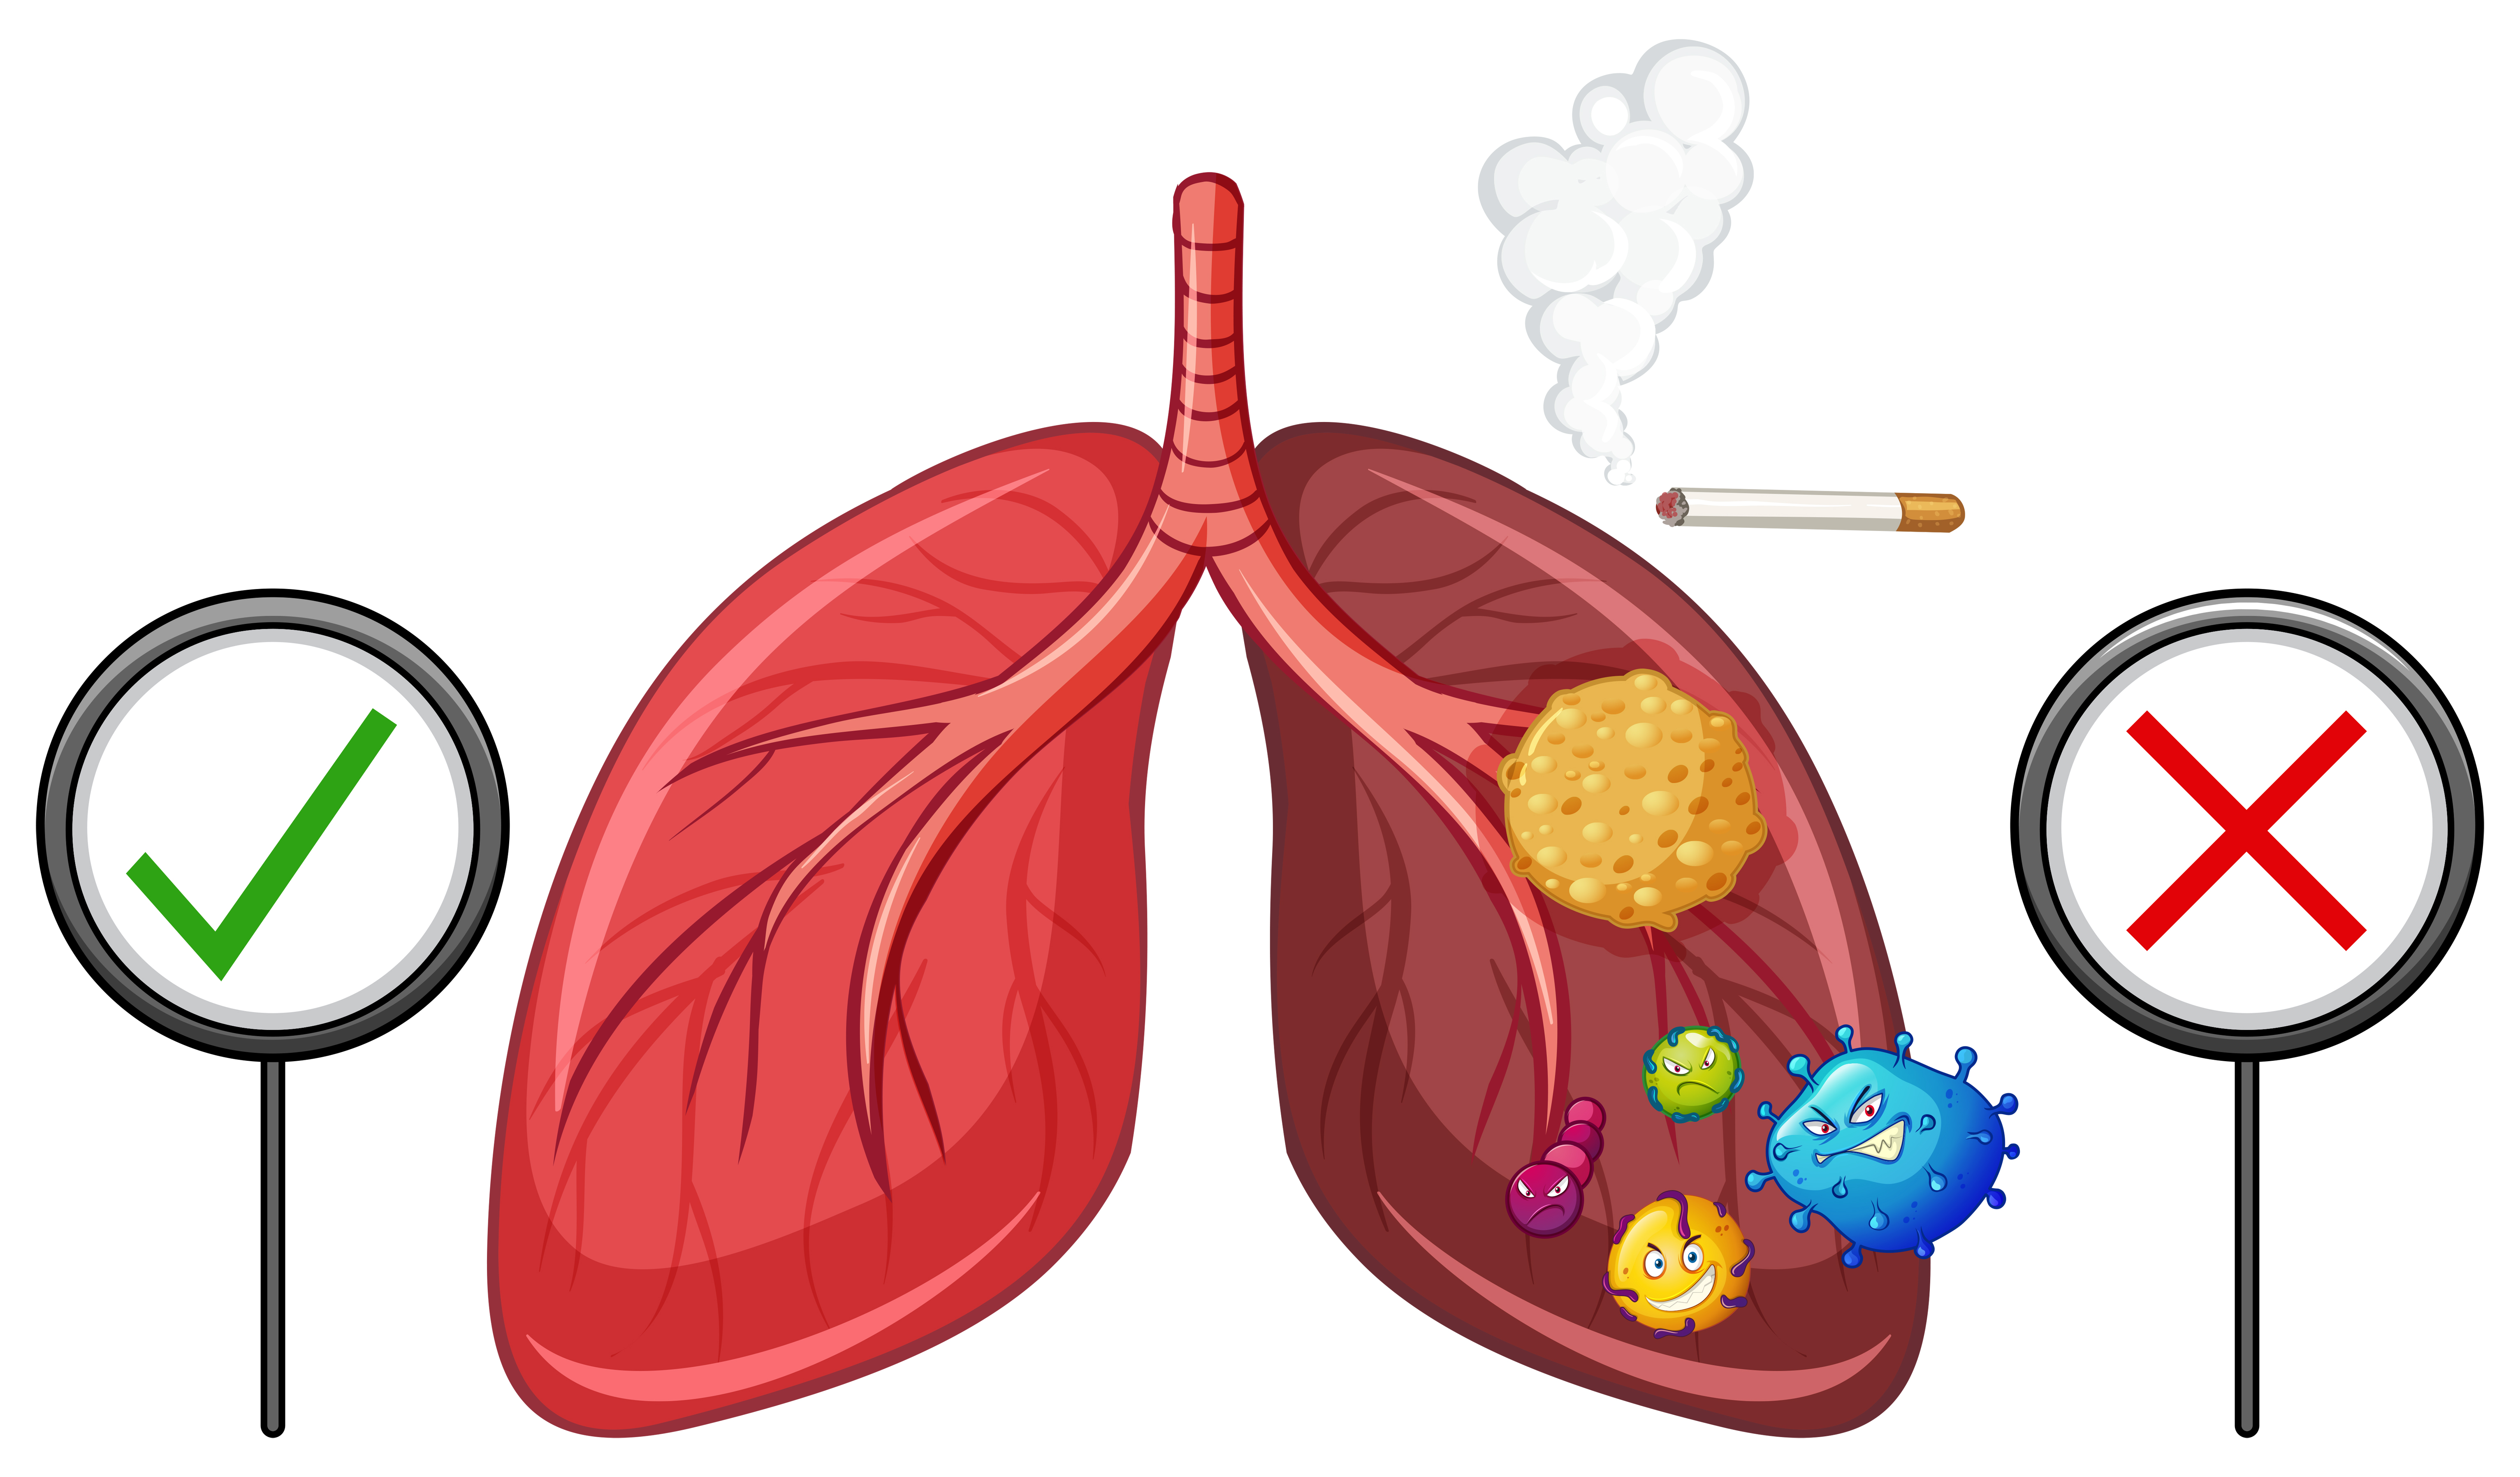

Здоровые Легкие Картинки

Здоровые Легкие Картинки 117 фото